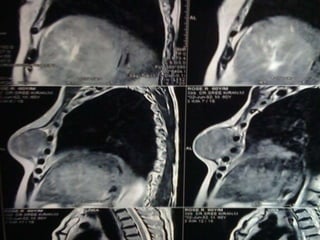

Hcc with sternal mets presentation

• 1.

UNUSUAL PRESENTATION OF HCC DR. RAJKUMAR, R. III YR POST GRADUATE DR. KALAICHELVI D.M. H.O.D. & PROF DEPT. OF MEDICAL ONCOLOGY MADRAS MEDICAL COLLEGE CHENNAI

• 2.

MR . X60/ M REFERRED FROM SGE I C/O SWELLING OVER THE ANT. CHEST WALL – 6 MONTHS . H/O PAIN FOR THE PAST- 2 WEEKS. NON ALCOHOLIC/ BEEDI SMOKER

• 3.

10×7 CM MASSOVER THE ANT. CHEST WALL FIRM IN CONSISTENCY P/A- HEPATOMEGALY

• 4.

INVESTIGATIONS • CBC- NORMAL •LFT- S. BILIRUBIN- 1.3 DIRECT- 0.9 ALK.POS- 80 T.PROT- 6.8 ALB- 3.7 • RFT- NORMAL • HbSAG- NEGATIVE • ANTI HCV- NEGATIVE • HIV I & II- NEGATIVE • ALPHA-FETO PROTEIN- 1.62 IU/ml • USG ABDOMEN- HETEROECHOIC LESION RIGHT LOBE OF LIVER-11.5×10.5 CM – • IMPRESSION- HCC Rt. LOBE OF LIVER

• 14.

HCC – METASTATIC •UNUSAL EXTRA HEPATIC METASTATIC SITE • NON CIRRHOTIC BACKGROUND • GOOD P.S. STATUS • BCLC STAGE C • SORAFENIB – 200 MG B.I.D. • PALLIATIVE R.T. - STERNUM